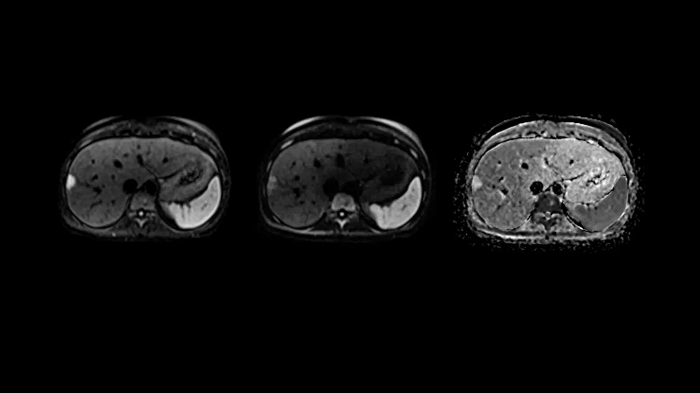

Body diffusion imaging

Outstanding quality diffusion imaging for comprehensive abdominal MR capabilities.

- Contour L Coil

- Spine Coil

Image Courtesy: University Hospital Erlangen, Germany | Image-ID: 4aaaa0339